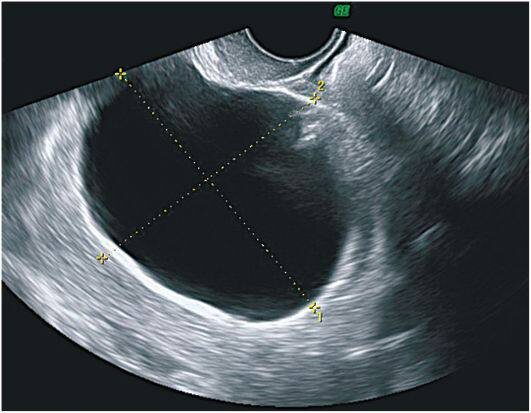

Врачи красноярской БСМП спасли 59-летнюю женщину с гигантской цистаденомой яичника.

Сообщается, что новообразование у пациентки впервые обнаружили четыре года назад. Кистозная опухоль постепенно увеличилась до внушительных размеров — более 60 сантиметров. В результате женщина даже потеряла возможность самостоятельно двигаться — не могла встать и вынуждена была находиться исключительно в положении лёжа на боку.